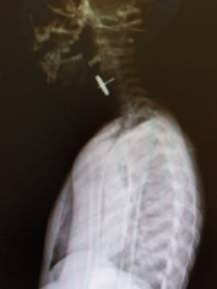

В поселке Магдагачи 3-летний мальчик проглотил колесико от машины, которое застряло в пищеводе. Из-за возможных тяжелых осложнений ребенок нуждался в срочной транспортировке в больницу более высокого уровня.

"Инородное тело представляло собой металлическую конструкцию на штыре до 1,5 см в длину с маятником округлой формы до 1,5 см в диаметре. Инородные тела такой сложной конфигурации опасны перфорацией органов, тканей и сосудов с дальнейшим развитием кровотечения и перитонита", - отметил Петр Ширяев.